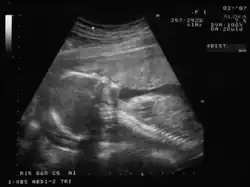

Ecografía de 20 semanas

Los signos positivos de certeza de un embarazo consisten en poder demostrar sin error la presencia de estructuras embrionarias mediante ultrasonido y otras imágenes radiológicas.

En cualquier momento del embarazo, en especial en presencia de un feto maduro en la segunda mitad del embarazo, es posible demostrar por ecografía transabdominal bidimensional o tridimensional tanto sus partes anatómicas como el saco vitelino.